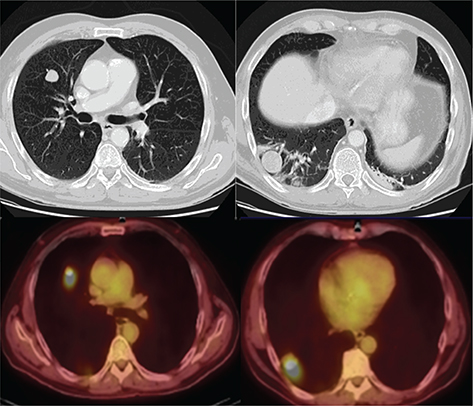

Fig 5

Figure 5. Pulmonary nodules. FDG PET/CT demonstrates hypermetabolic activity within two right lung pulmonary nodules. This patient was status post left testicular mass resection revealing a nonseminomatous germ cell tumor with pathologic staging of pT4 Nx Mx. Findings on PET/CT were consistent with pulmonary metastases resulting in final staging of T4 N0 M1.